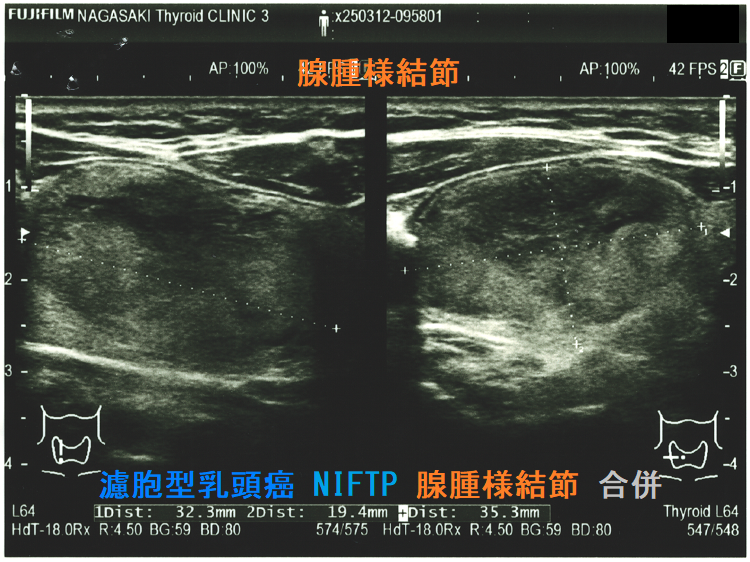

Non-invasive follicular thyroid neoplasm with papillary-like nuclear features (NIFTP) 超音波(エコー)画像;見かけは濾胞型甲状腺乳頭癌、 濾胞性腫瘍、腺腫様結節と鑑別できまない

Non-invasive follicular thyroid neoplasm with papillary-like nuclear features (NIFTP) 超音波(エコー)画像 (水平断)

Non-invasive follicular thyroid neoplasm with papillary-like nuclear features (NIFTP)の超音波(エコー)所見は、

- 被膜が存在(被膜のない場合もある)

- 充実性、等エコーが多い

- 砂粒状石灰化を認めない

などで、濾胞型甲状腺乳頭癌、濾胞性腫瘍(良性濾胞腺腫 、甲状腺濾胞癌)と鑑別できません。砂粒状石灰化のない濾胞型甲状腺乳頭癌なんて普通に存在します。NIFTPの60.1%は悪性を疑う所見が無いとされます[Endocrine. 2021 Jul;73(1):131-140.]。